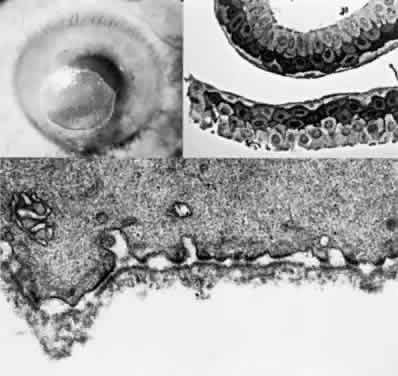

OCULAR FINDINGS. The outstanding clinical feature common to all three phenotypes is the corneal and conjunctival cystine crystal deposition (Figs. 3 and 4). Photophobia is often the only presenting visual symptom; this may be incapacitating and associated with blepharospasm.

Fig. 3. Cystinosis. Refractile crystals noted throughout the corneal stroma.

Fig. 4. Cystinosis. Top, Transmission electron micrograph showing a stromal keratocyte containing a number of needle-shaped crystalline profiles limited by unit membranes. (× 19,000.) Bottom, Electron micrograph of conjunctival fibrocyte revealing crystalline profiles of sparse granular material within membrane-limited lysosomes. (× 30,000.) (Courtesy of Dr. Kenneth Kenyon)

Corneal deposits appear as a layer of homogeneously distributed, fusiform or needle-shaped, iridescent crystals situated in the stroma beneath the epithelium. In the infantile form, anterior crystal deposition begins early in life (between 6 and 15 months of age) and proceeds posteriorly as the patient ages; deposition advances more rapidly in the periphery. The anterior location of the crystals may be associated with recurrent erosions.33 The depth of the stromal deposition and the density of crystals is always greater peripherally than centrally. More and larger crystals occur in the superficial stroma. No visual impairment occurs at this early stage. By the age of 7 years, most patients have crystals, either within or on the endothelial surface34,35; markedly decreased corneal sensitivity is also present.36 The spherical contrast sensitivity function is significantly lower in infantile cystinosis than in age-matched controls.37

The retinal abnormality consists of a generalized depigmentation that may assume a patchy pattern. At first the pigmentary disturbance tends to be peripheral, but it progresses with age. Macular abnormalities have been observed.39 Intracellular crystals also have been seen in the retinal pigment epithelial cells during electron microscopy.